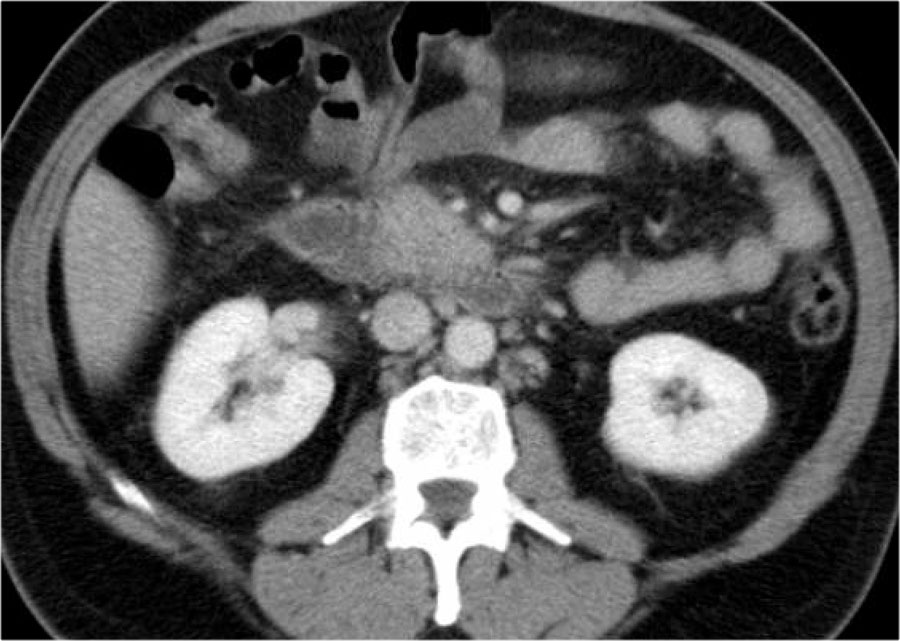

Các hình ảnh thuộc về một bệnh nhân viêm tụy cấp.

Trên hình ảnh phía trên là một ổ dịch ở vùng đầu tụy trong khoang cạnh thận trước bên phải.

Ở giai đoạn này, không thể phân biệt giữa ổ dịch quanh tụy cấp tính và ổ hoại tử cấp tính.

Trên phim chụp theo dõi, ổ dịch ở khoang cạnh thận trước bên phải tăng kích thước.

Ổ dịch có tỷ trọng dịch và thành mỏng ngấm thuốc.

Đây có thể là nang giả tụy hoặc ổ hoại tử được bao bọc, có thể nhiễm trùng hoặc không.

Bệnh nhân tiến triển nhiễm khuẩn huyết và được dẫn lưu qua da.

Sau dẫn lưu, kích thước ổ dịch hầu như không giảm.

Bệnh nhân được phẫu thuật và ổ dịch được phát hiện chứa đầy mảnh vụn hoại tử, điều này không được nhận ra trên CT, do đó đây là ổ hoại tử được bao bọc chứ không phải nang giả tụy.

Các mảnh vụn hoại tử quá đặc để có thể dẫn lưu qua da thành công.